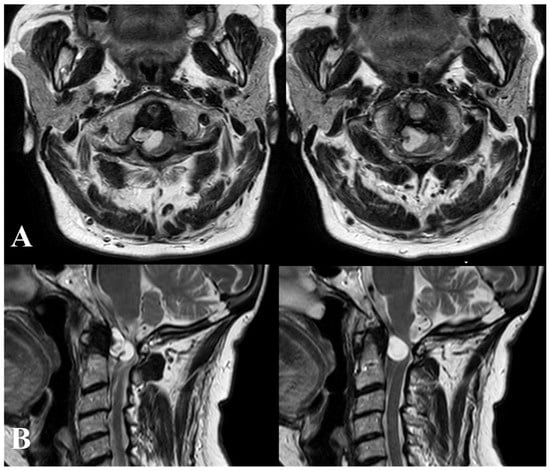

A 56-year-old woman was admitted to our institution due to a sudden onset of right hemiparesis following three days of neck pain. Upon examination, she exhibited hemi-hyposthenia (BMRC 3/5), inability to stand or walk, heightened deep tendon reflexes bilaterally (particularly on the right side), and bladder dysfunction. Additionally, she displayed nuchal rigidity and positive Kernig and Brudzinski signs. Initial hematological and coagulation tests yielded unremarkable results, and the patient had no history of vertebral trauma. Considering the abrupt symptom onset, suspicions arose regarding either a malignancy or hemorrhage from a vascular malformation. Given the concurrent presence of meningeal signs, emergency computed tomographic (CT) scanning from the brain down to the craniovertebral junction (CVJ) was conducted. The CT scan revealed an iso-hyperdense lesion at the CVJ. Subsequent T1- and T2-weighted magnetic resonance imaging (MRI) identified a large anterior, right lateral tumor measuring approximately 1.3 × 1.6 cm at the C1–C2 level. The tumor appeared hyperintense in T2WI and hypointense in T1WI, exhibiting ring enhancement after gadolinium administration (Figure 2 and Figure 3).

Figure 2.

T2-weighted magnetic resonance imaging (MRI) axial (A) and sagittal (B) images revealing a large anterior, right lateral tumor measuring approximately 1.3 × 1.6 cm at the C1–C2 level. The tumor displays hyperintensity in T2-weighted imaging (T2WI).